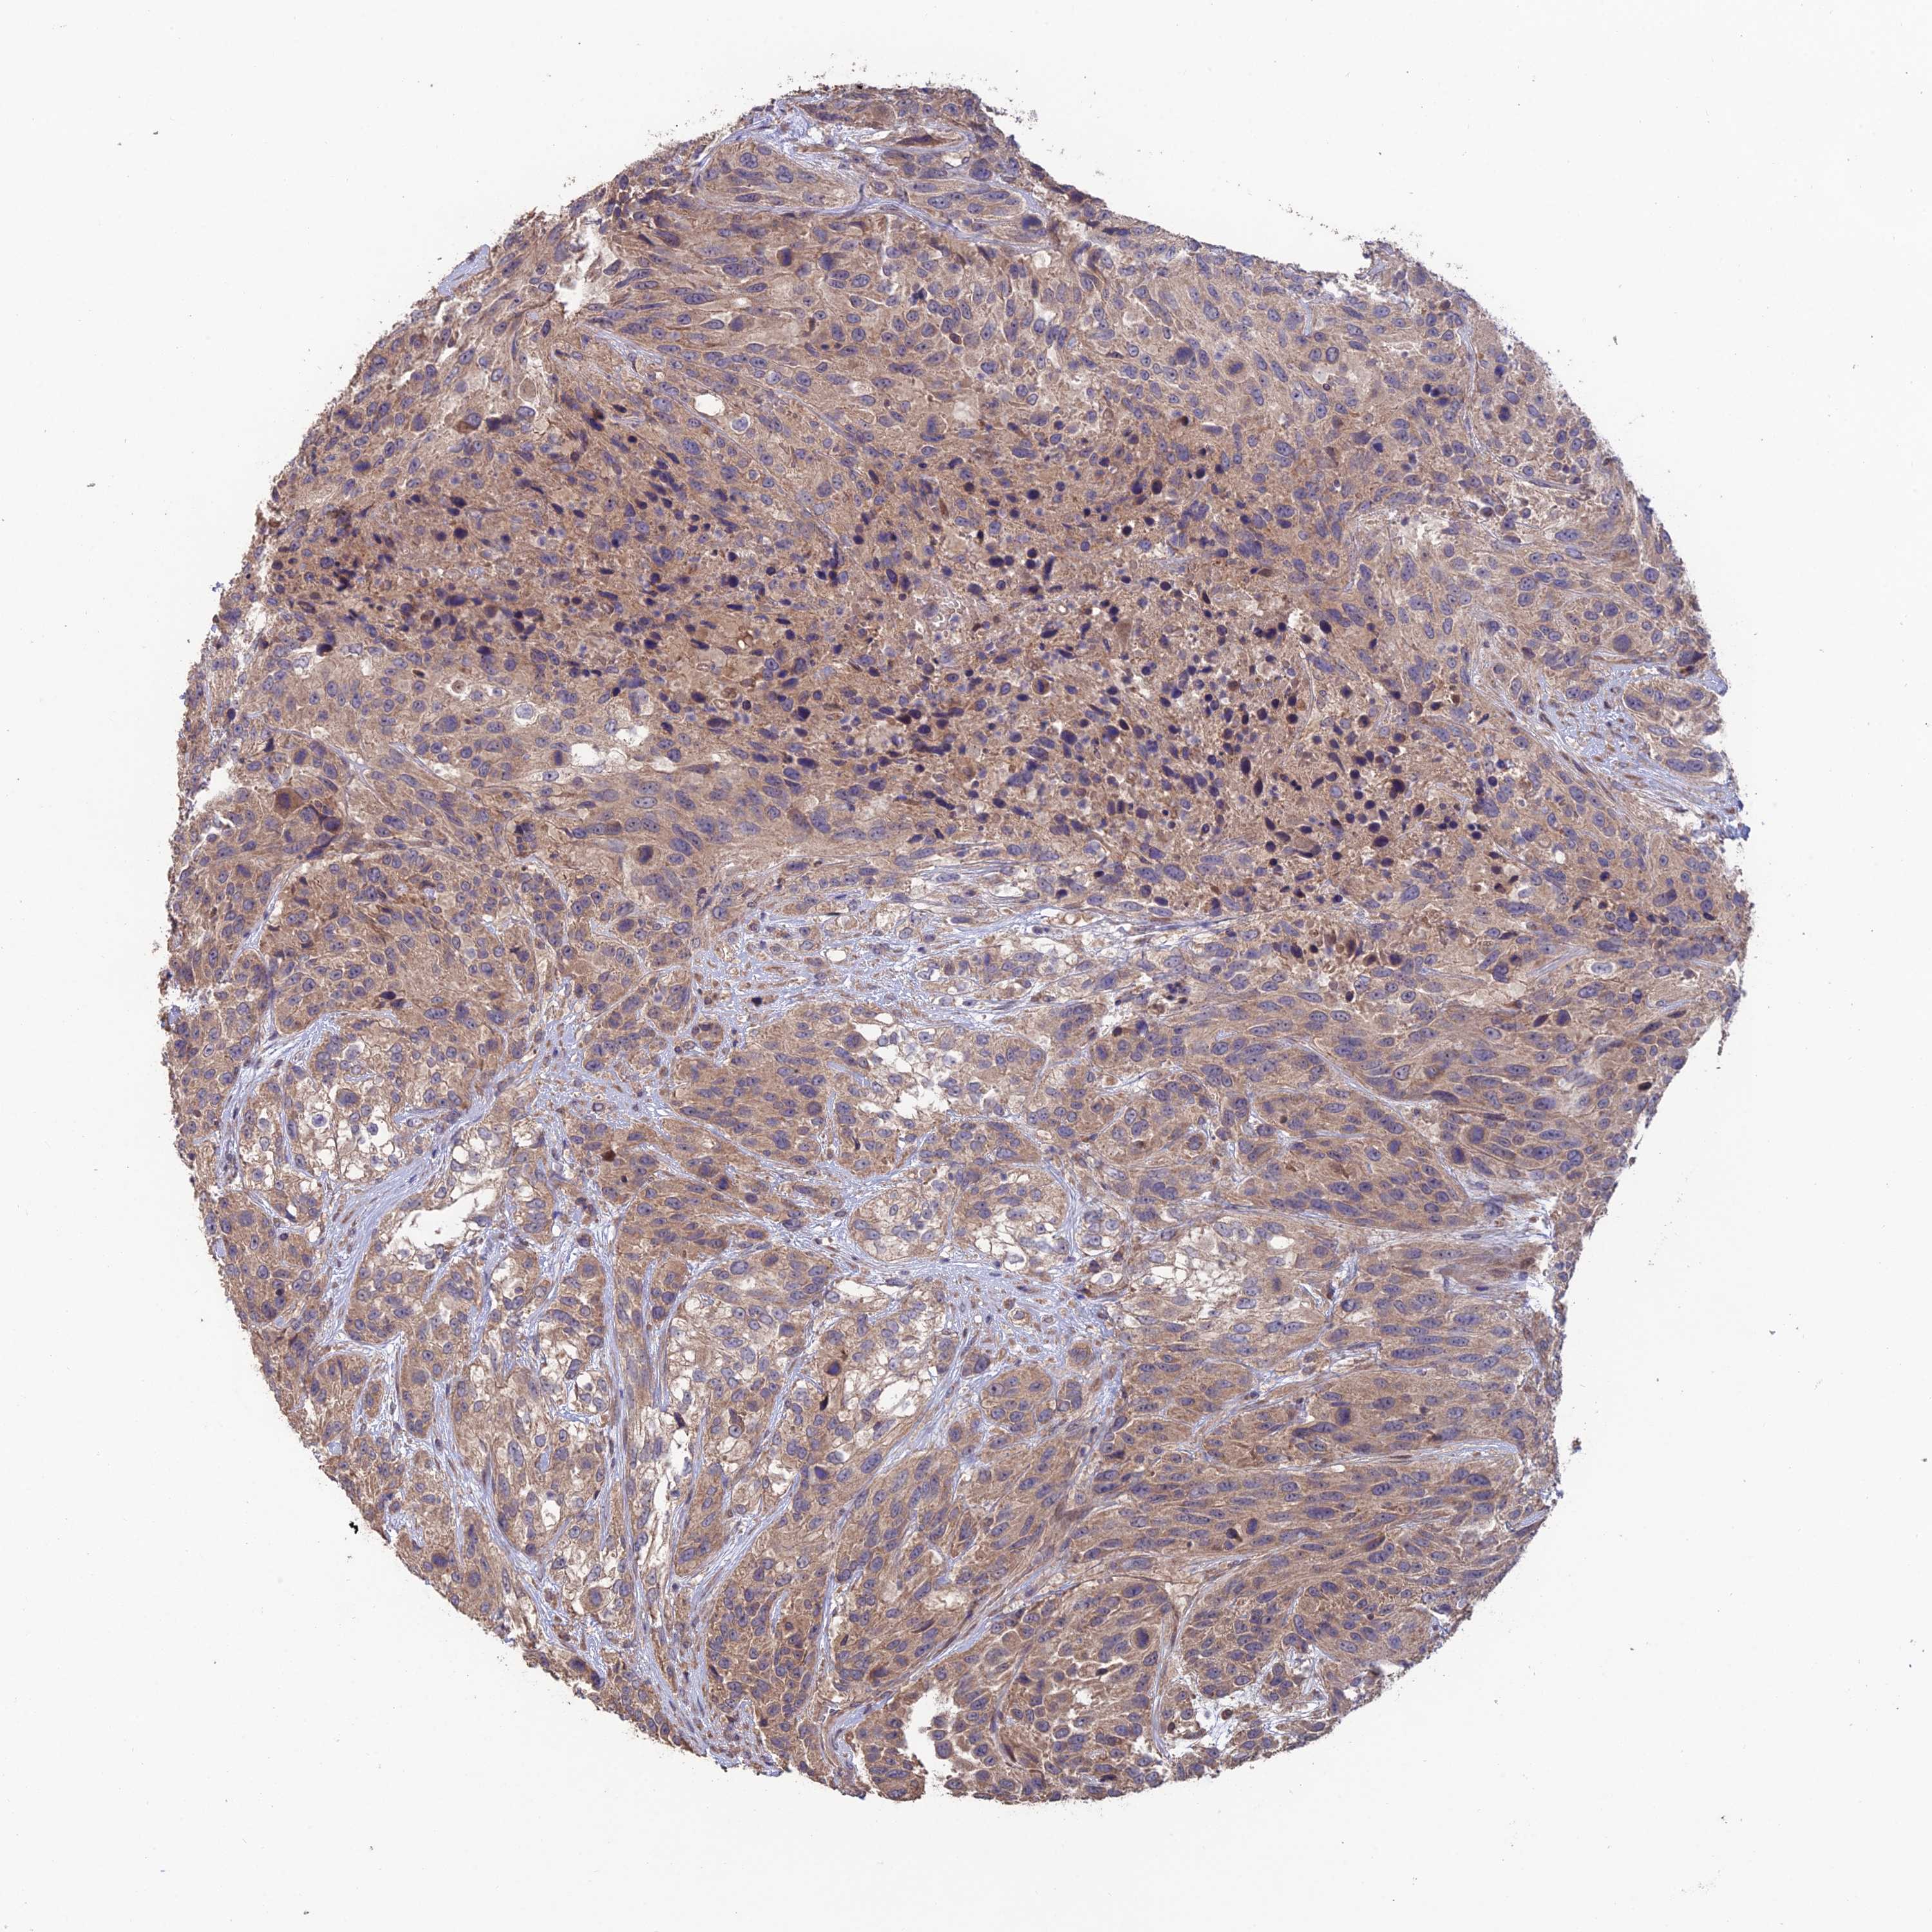

UROTHELIAL CANCER - Protein expressioni

A mouse-over function shows sample information and annotation data. Click on an image to view it in a full screen mode. Samples can be filtered based on level of antibody staining by selecting one or several of the following categories: high, medium, low and not detected. The assay and annotation is described here.

Note that samples used for immunohistochemistry by the Human Protein Atlas do not correspond to samples in the TCGA dataset.

Antibody stainingi

Antibody staining in the annotated cell types in the current human tissue is reported as not detected, low, medium, or high, based on conventional immunohistochemistry profiling in selected tissues. This score is based on the combination of the staining intensity and fraction of stained cells.

Each image is clickable and will lead to virtual microscopy that enables deeper exploration of all samples and also displays staining intensity scores, fraction scores and subcellular localization as well as patient and tissue information for each sample.

Antibody HPA042295

Staining

High

Medium

Low

Not detected

Intensity

Strong

Moderate

Weak

Negative

Quantity

>75%

75%-25%

<25%

None

Location

Nuclear

Cytoplasmic/membranous

Cytoplasmic/membranous,nuclear

Urothelial carcinoma, High grade

Urothelial carcinoma, Low grade